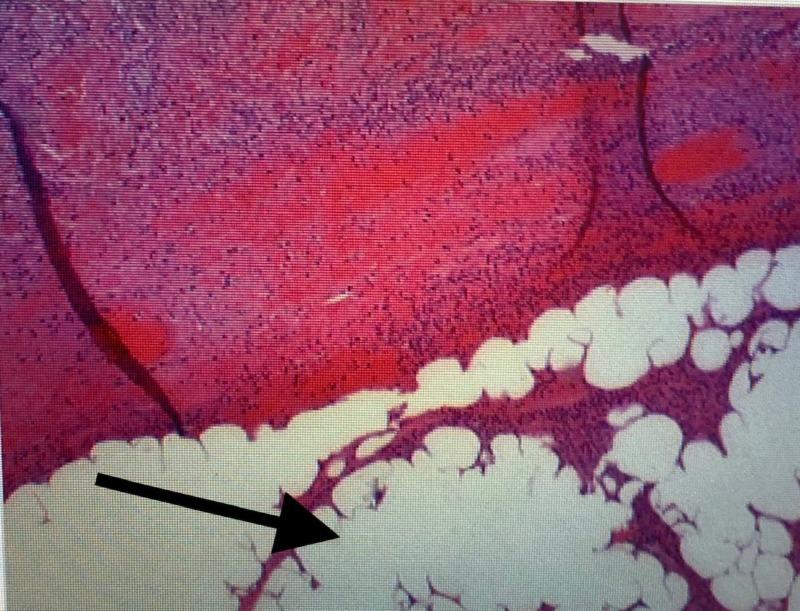

Intussusception is a rare cause of bowel obstruction caused by both benign and malignant pathology. We are presenting the case of an elderly patient who had been diagnosed with irritable bowel syndrome for many years prior to presenting to us with ileocecal intussusception causing a small bowel obstruction. Laparoscopic resection of the terminal ileum and cecum was performed. Pathology revealed multiple submucosal lipomas as the underlying cause.

肠套叠是由良性和恶性病变引起的肠梗阻的罕见原因。我们报告一例老年患者,该患者在因回盲部肠套叠导致小肠梗阻前来就诊之前,多年来一直被诊断为肠易激综合征。进行了腹腔镜下末端回肠和盲肠切除术。病理显示多个黏膜下脂肪瘤是潜在病因。